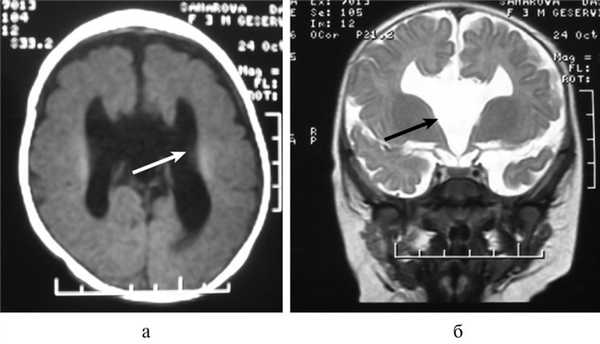

Важной находкой при АМТ на МРТ является параллельная ориентация тел боковых желудочков по отношению друг к другу (рис. 4, а), расширенные фронтальные отделы желудочков, так называемый «симптом ухвата».

Рис. 4. МРТ головного мозга больной К., 4 года. АМТ. Аксиальная проекция: а — аномальная параллельная ориентация тел боковых желудочков по отношению друг к другу (стрелка); б — фронтальное сечение: деформация передних и задних рогов боковых желудочков, своеобразный U-образный характер фронтальных отделов боковых желудочков (стрелка).